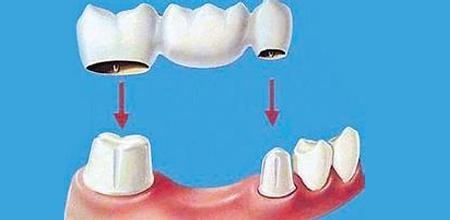

固定桥修复

固定桥的结构就像是一座桥梁,缺牙间隙部分是桥梁的身体,缺牙间隙两边的健康牙齿(牙基)是两个桥头(见上图)。在牙齿修复完成之后,缺失的牙齿就和它前后两颗牙齿连接成了一个整体。